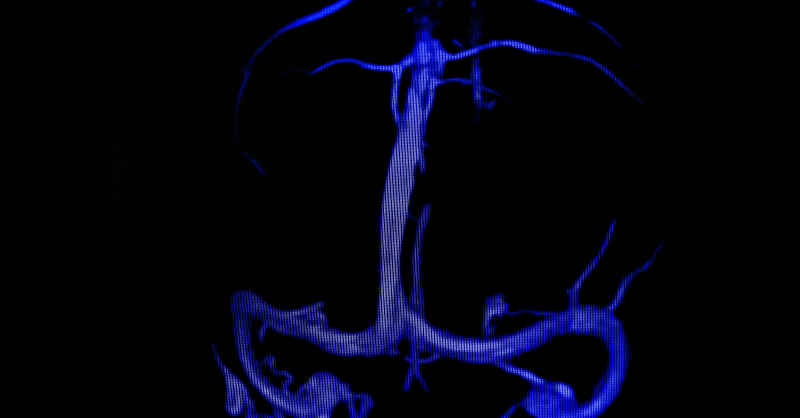

Dúplex

Fusionando ecografía y doppler, mi enfoque tridimensional ofrece un diagnóstico vascular integral y extraordinariamente preciso.